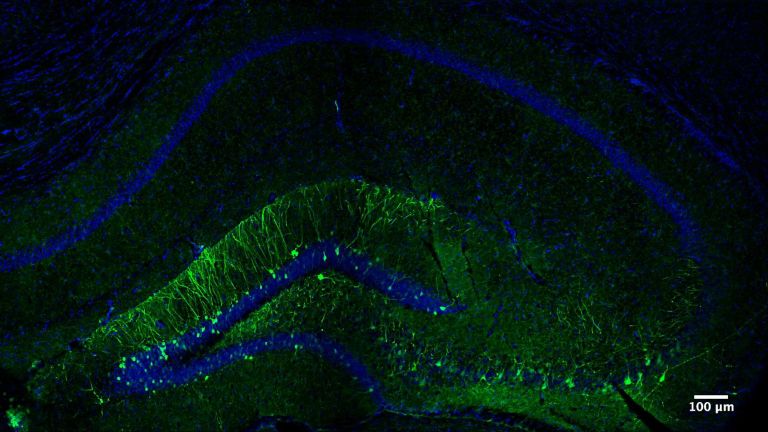

- Bei einer Operation, die HMs Epilepsie lindern sollte, wurde beidseitig fast komplett der Hippocampus entfernt, eine kleine Struktur, die jedoch für das Einspeisen neuer Erinnerungen von zentraler Bedeutung ist.

Der Hippocampus ist der größte Teil des Archicortex und ein Areal im Temporallappen. Er ist zudem ein wichtiger Teil des limbischen Systems. Funktional ist er an Gedächtnisprozessen, aber auch an räumlicher Orientierung beteiligt. Er umfasst das Subiculum, den Gyrus dentatus und das Ammonshorn mit seinen vier Feldern CA1-CA4.

Offenbar hatte Karl Lashley bei seinen Studien am falschen Ort gesucht. In seinen Rattenexperimenten hatte er stets Teile der Hirnrinde, also der äußersten Schicht des Gehirns entfernt. Dieses Hirnareal ist in der Entwicklungsgeschichte des Gehirns das jüngste, alle anderen hielt Lashley für zu primitiv. H.M. fehlte es aber nicht an Hirnrinde, Scoville hatte einen Teil des Mandelkerns, der Amygdala, entfernt und fast den gesamten Hippocampus. Diese Region an der Innenseite der Schläfenlappen war offenbar entscheidend für das Formen neuer Erinnerungen.

Das zeigte sich auch in Tierversuchen. „Nach den Erfahrungen mit H.M. sind tausende Untersuchungen an Ratten und anderen Tieren gemacht worden“, sagt Markowitsch. Sie alle zeigten dasselbe: Wird der Hippocampus beschädigt, beeinträchtigt das die Fähigkeit, neue Erinnerungen abzuspeichern. Buschhäher finden das Essen, das sie versteckt haben, nicht wieder und Ratten finden sich in Labyrinthen nicht mehr zurecht.

Eine weitere Merkwürdigkeit im Fall H.M: Ihm fehlte zwar das Langzeitgedächtnis, aber für ein paar Sekunden konnte er sich alles merken. Viele Versuche haben gezeigt, dass sein Kurzzeitgedächtnis in etwa so gut funktionierte wie das eines gesunden Menschen. Telefonnummern oder Wortlisten etwa konnte H.M. sich kurze Zeit merken, wurde er aber nach ein paar Minuten oder Stunden noch einmal gefragt, hatte er sie vergessen. „H.M. war der Paradefall, der gezeigt hat, dass der Hippocampus zentral ist für die Übertragung vom Kurzzeit– ins Langzeitgedächtnis“, sagt Markowitsch. Was auf lange Zeit abrufbar bleiben soll, das muss offenbar durch das Nadelöhr des Hippocampus. So haben Forscher mit bildgebenden Verfahren gezeigt, dass sich Menschen aus einer Liste von Wörtern an die am besten erinnern, bei deren Lernen der Hippocampus am stärksten aktiv war.

Der Hippocampus ist der größte Teil des Archicortex und ein Areal im Temporallappen. Er ist zudem ein wichtiger Teil des limbischen Systems. Funktional ist er an Gedächtnisprozessen, aber auch an räumlicher Orientierung beteiligt. Er umfasst das Subiculum, den Gyrus dentatus und das Ammonshorn mit seinen vier Feldern CA1-CA4.

Der Hippocampus ist der größte Teil des Archicortex und ein Areal im Temporallappen. Er ist zudem ein wichtiger Teil des limbischen Systems. Funktional ist er an Gedächtnisprozessen, aber auch an räumlicher Orientierung beteiligt. Er umfasst das Subiculum, den Gyrus dentatus und das Ammonshorn mit seinen vier Feldern CA1-CA4.